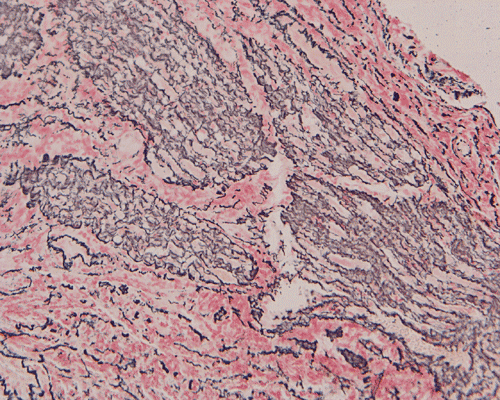

The surgery removed several irregular fragments of tan, soft tissue for examination that were 2.5 x 1.2 x 1.0 cm in toto. Histologically, the lesion is a highly cellular neoplasm with tumor cells packed in solid sheets and without a specific architectural pattern (Panel D). Small, focal necrosis is also present (not shown). The tumor has rich vascularity and the endothelial cells seem to be active (Panel E). Almost all the tumor cells have only a thin rim of amphophilic cytoplasm, large nuclei with prominent nucleoli (Panel E and F). Clear cytoplasm is present in some tumor cells. In general, the cells do not look epithelioid or spindle. In some of the tissue fragment, the tumor shows invasion into the peripheral nerve root with dissection of the nerve fibers (Ú in Panel G and H). This phenomenon is well demonstrated by reticulin stain (Panel I) and immunohistochemistry for neurofilament proteins (Panel J). About half of the tumor cells are strongly positive for vimentin (Panel K). There is also scant positive tumor cells for S100 protein (Panel L) and cytokeratin AE1/3 (Panel M). The tumor cells are negative for neuorfilament proteins (Panel K) and smooth muscle protein (Panel N).